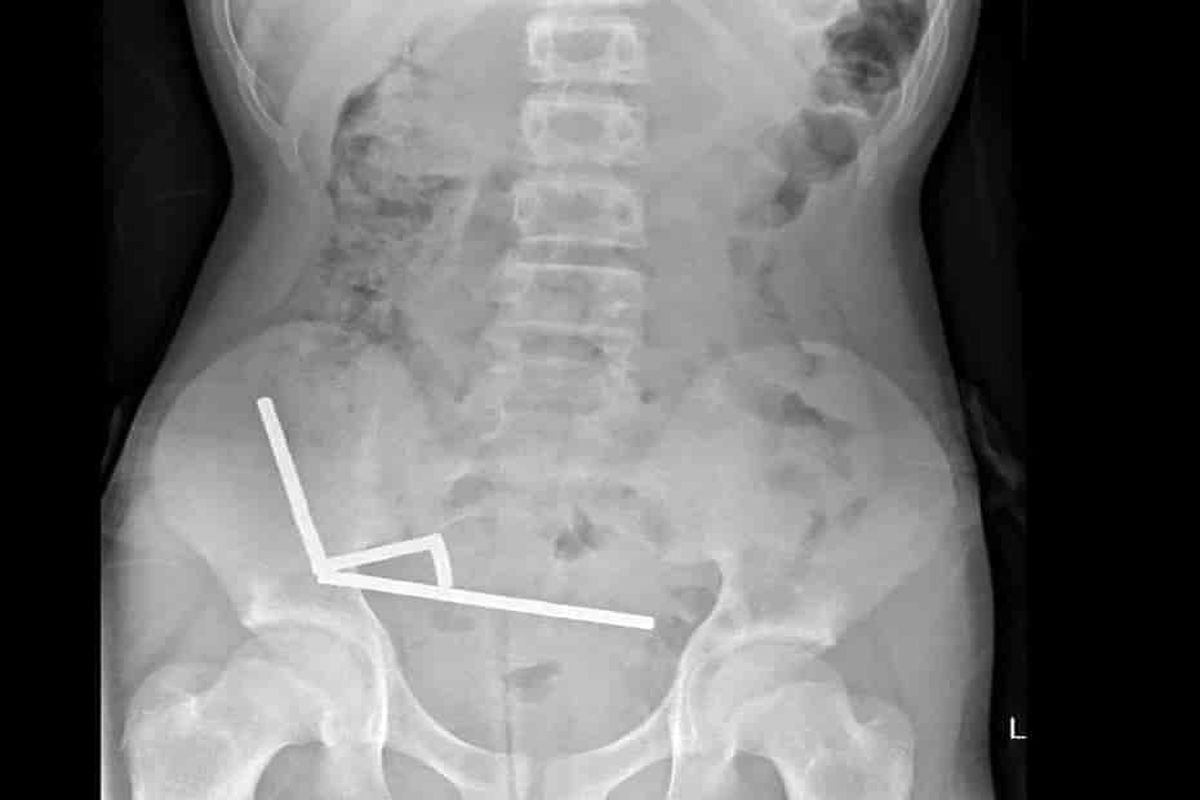

این آهنرباها که از ژانویه ۲۰۱۳ در نیوزیلند ممنوع شده‌اند، از طریق پلتفرم خرید آنلاین «تیمو» خریداری شده بودند. تصاویر رادیولوژی نشان داد که این آهنرباها در چهار خط مستقیم در روده نوجوان تجمع کرده‌اند و به دلیل نیروی مغناطیسی، بخش‌های جداگانه روده به هم چسبیده بودند.